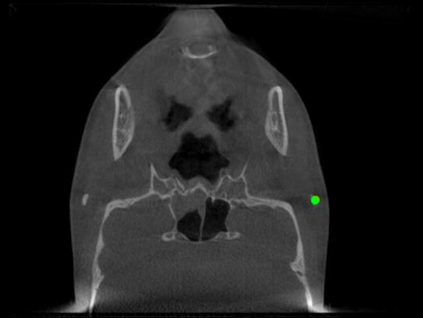

Detecting 3D landmarks on cone-beam computed tomography (CBCT) is crucial to assessing and quantifying the anatomical abnormalities in 3D cephalometric analysis. However, the current methods are time-consuming and suffer from large biases in landmark localization, leading to unreliable diagnosis results. In this work, we propose a novel Structure-Aware Long Short-Term Memory framework (SA-LSTM) for efficient and accurate 3D landmark detection. To reduce the computational burden, SA-LSTM is designed in two stages. It first locates the coarse landmarks via heatmap regression on a down-sampled CBCT volume and then progressively refines landmarks by attentive offset regression using multi-resolution cropped patches. To boost accuracy, SA-LSTM captures global-local dependence among the cropping patches via self-attention. Specifically, a novel graph attention module implicitly encodes the landmark's global structure to rationalize the predicted position. Moreover, a novel attention-gated module recursively filters irrelevant local features and maintains high-confident local predictions for aggregating the final result. Experiments conducted on an in-house dataset and a public dataset show that our method outperforms state-of-the-art methods, achieving 1.64 mm and 2.37 mm average errors, respectively. Furthermore, our method is very efficient, taking only 0.5 seconds for inferring the whole CBCT volume of resolution 768$\times$768$\times$576.